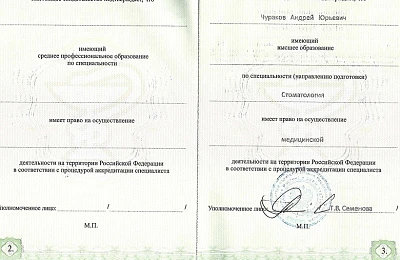

Сертификаты и лицензии

Образование

Пермская государственная медицинская академия им. акад. Е.А. Вагнера (стоматология), базовое образование